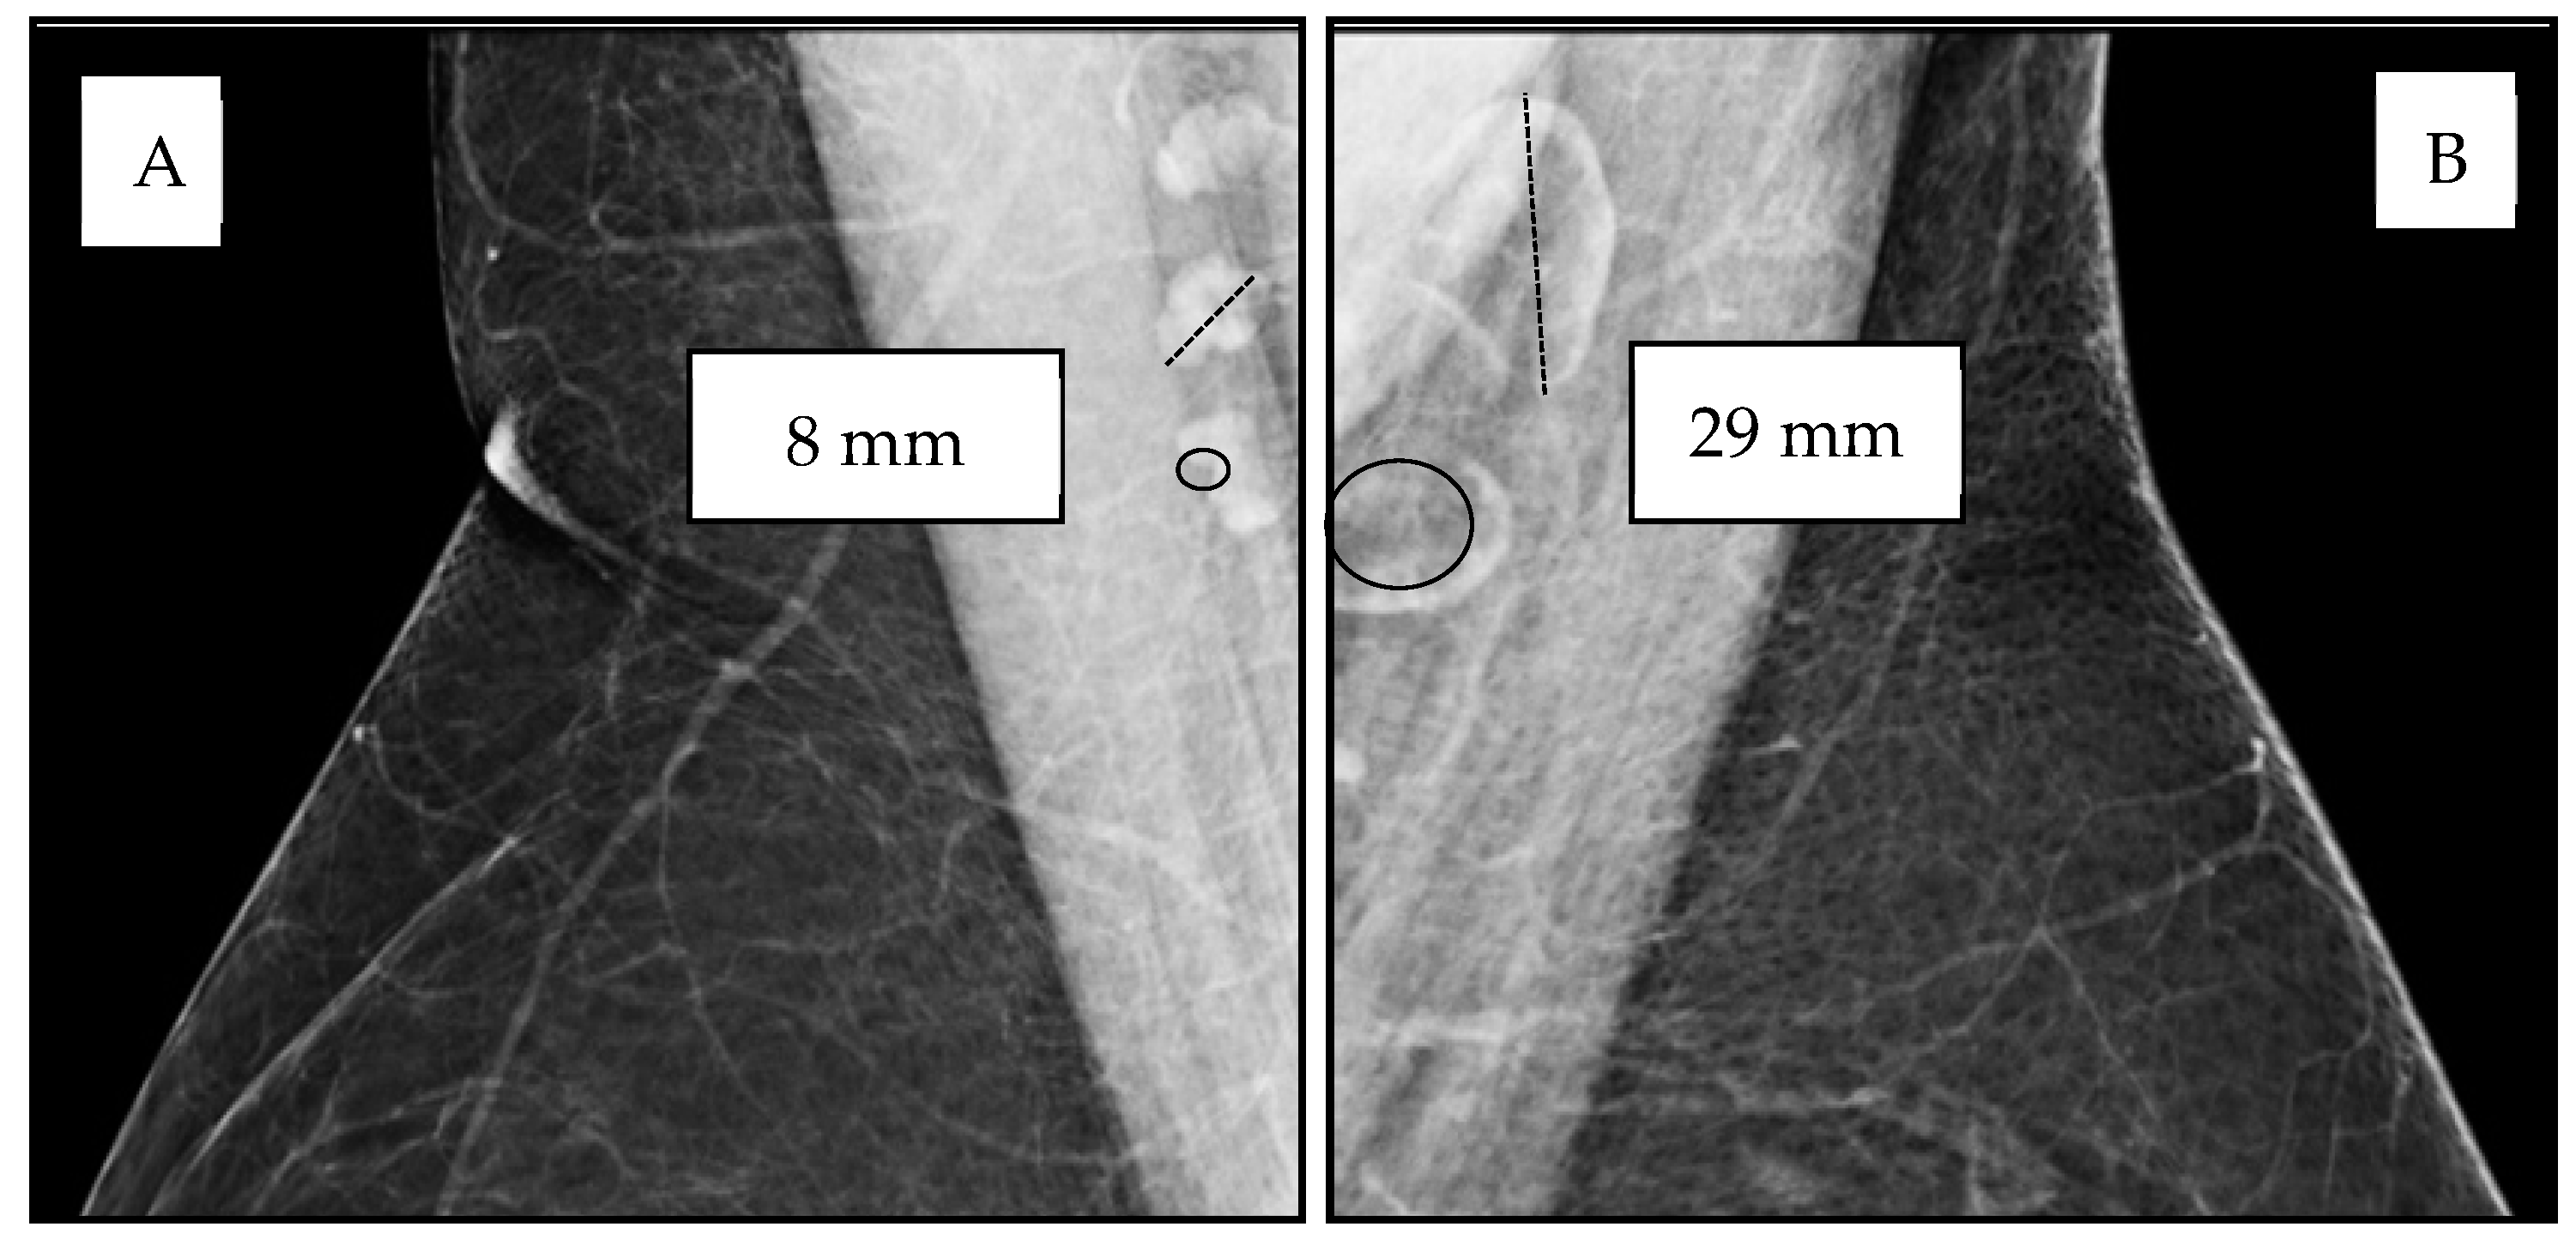

Lymph node adiposity (LNA) is a novel marker of ectopic adiposity within the immune system that can be readily evaluated on screening mammography recommended in the United States for all women ages 40–74. Axillary lymph nodes are well visualized in most breast imaging studies, and they demonstrate differences in size and architecture due to increased ectopic adipose deposition within the lymph node (LN) hilum, resulting in an increase in overall LN size due to fat expansion of the LN (Figure 1). Lymph nodes are secondary lymphoid organs of the immune–lymphatic system embedded within adipose tissue throughout the body. Studies have shown a significant association between BMI and enlarged axillary lymph nodes due to increased fat accumulation within the LN hilum, independent of age and breast density [14,15]. While LNA is associated with an increase in LN length and LN width, LN length is the largest metric of LN size with the highest sensitivity for adverse health outcomes and the best inter-rater agreement (Figure 1) [14]. Based on our studies, most normal axillary LNs measure in the range of 6–15 mm and may increase in size when enlarged by ectopic fat deposition, occasionally reaching a size of 50 mm [14,15,16,17,18,19,20]. Lymph node morphology allows for the definitive discrimination between increased size due to benign adipose deposition versus increased size due to reactive or malignant adenopathy. Unlike the assessment of other ectopic fat depots requiring advanced imaging, LNA is easily assessed on screening mammograms, an imaging exam that is widely utilized to screen for breast cancer among women above the age of 40 [14,15].

Figure 1.

Variable lymph node size and morphology on mammographic medio-lateral oblique (MLO) views of the axilla. (A) Normal axillary lymph nodes measuring 8–11 mm (dotted line) with small physiologic “fatty notch” of lucent hilar fat (circle). (B) Fat-enlarged axillary lymph nodes measuring 25–29 mm (dotted line) due to increased lucent hilar fat (circle).